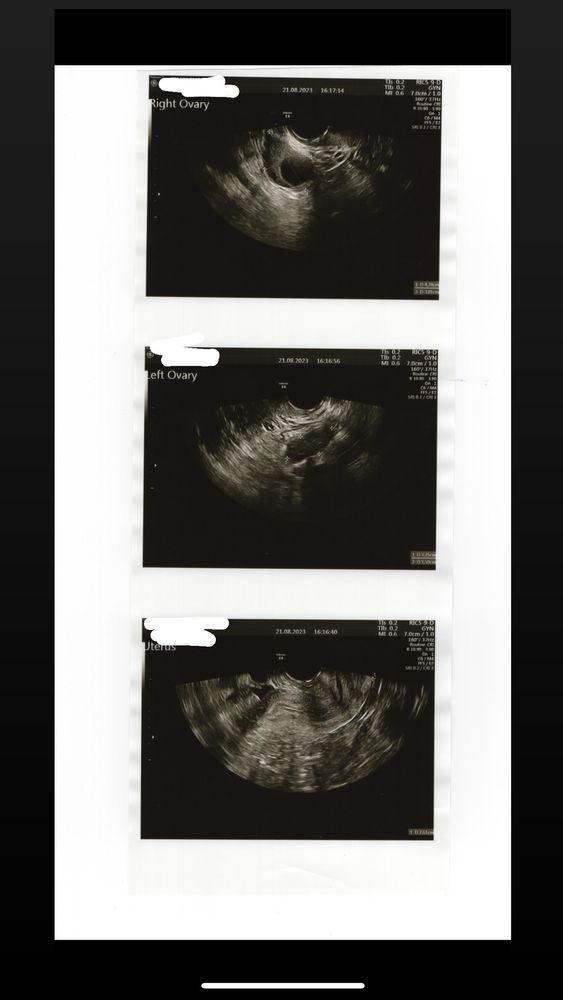

Фолликулометрияузи на 14 ДЦ

у меня МФЯ точно , но смотрела другие узи , обычно фолликулов больше..

узи на 14 ДЦ